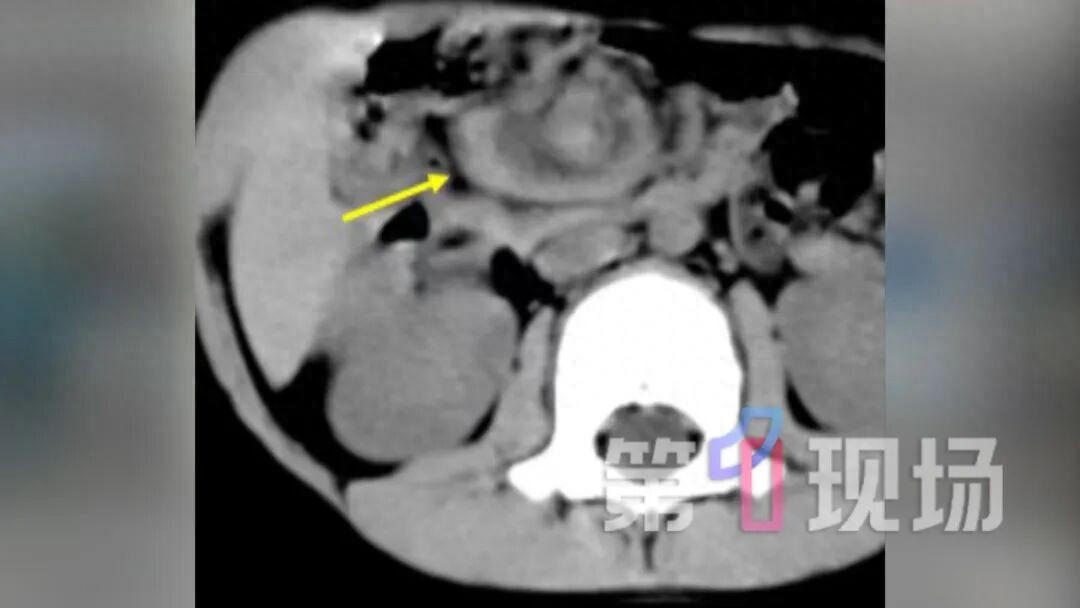

孩子腹痛、呕吐本来应该是常见症状 但有一种情况 家长如果忽视就有可能酿成悲剧 近日,深圳坪山区妇幼保健院小儿外科团队连续成功救治了两名“肠扭转”急症患儿,医生称:“胆汁性呕吐(呈黄绿色)伴随突发剧烈腹痛”,是肠扭转的最高级别警报,必须立即送医。 胆汁性呕吐+突发剧痛 家长紧急送医 4岁的乐乐(化名)在饭后玩耍时突然大喊“肚子疼”。起初,母亲张女士以为是普通胃肠炎,没有引起重视。然而,乐乐的病情迅速加重,发展为剧烈腹痛,并频繁吐出黄绿色的呕吐物,很快面色苍白、精神萎靡。当晚张女士紧急就带着乐乐去了医院。 深圳市坪山区妇幼保健院医师 小儿外科主任 张镟 我们高度怀疑他是小肠扭转的情况。 CT做完后,当天晚上12点我们就把患者送到手术室做了腹腔镜的探查,证实了他是先天性肠旋转不良,伴有中肠扭转了720度,相当于肠子转了两圈。

医疗团队争分夺秒为乐乐实施了急诊腹腔镜微创手术。手术中发现,乐乐的肠管及供应血管拧了一个“**花”。万幸,家属送医相对及时,经过手术和精心的护理,乐乐的肠管得以保住,后续已顺利康复出院。